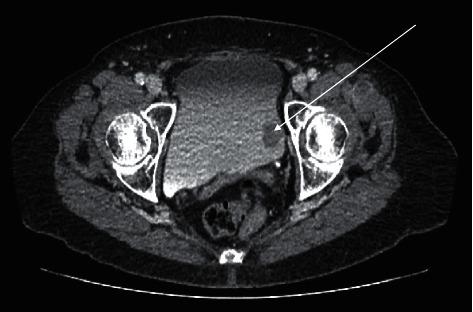

Bladder metastasis from cutaneous melanoma is a rare pathology. A 79-year-old woman presented to the haematuria clinic on account of painless visible haematuria. Ten years prior to this index presentation, she was diagnosed with melanoma on her right thigh following a total excision of the skin lesion. Cystoscopy showed a pigmented bladder tumour, and the histology report following a transurethral resection was consistent with metastatic melanoma, and further imaging revealed metastasis to the lungs, adrenals, and lymph nodes.

皮肤黑色素瘤的膀胱转移是一种罕见的病理情况。一名79岁女性因无痛性肉眼血尿就诊于血尿诊所。在此次就诊前十年,她右侧大腿的皮肤病变经完全切除后被诊断为黑色素瘤。膀胱镜检查显示有一个色素沉着的膀胱肿瘤,经尿道切除后的组织学报告与转移性黑色素瘤相符,进一步的影像学检查显示已转移至肺、肾上腺和淋巴结。